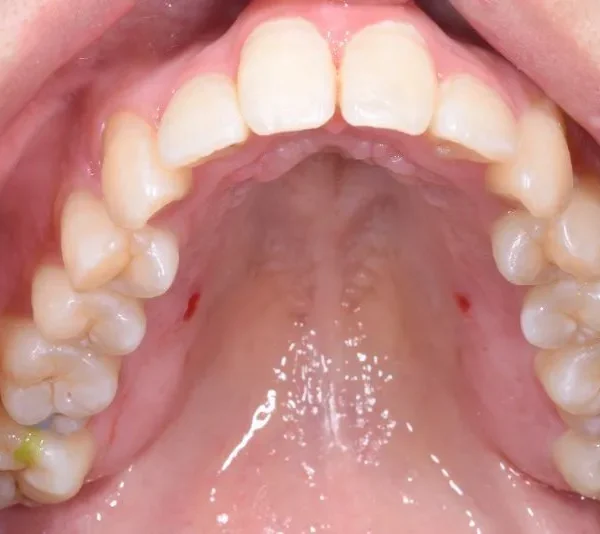

【大人の矯正】叢生・八重歯・交叉咬合・非抜歯症例・19歳女性【R.T様】

初診時年齢 19~29歳 (女性) 主訴 ガタガタ・交叉咬合が気になる

診断名 叢生・交叉咬合 装置名

ガタガタ・八重歯を主訴に来院された患者様です。

初診